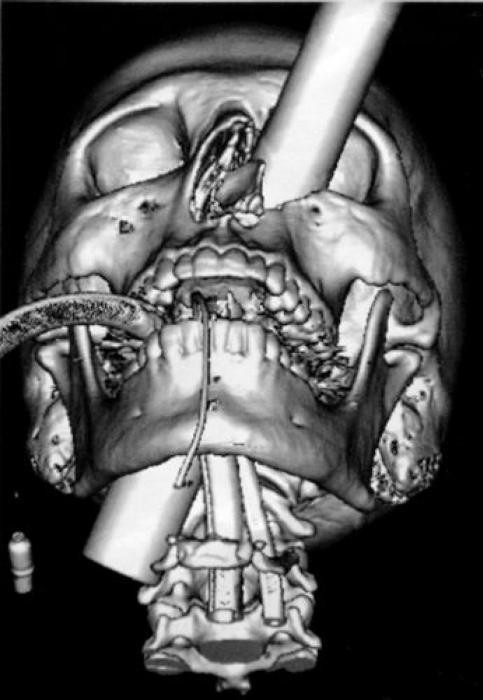

Accident, incident de pistolet à clous ou introductions douteuses de choses douteuses dans des parties douteuses de leur corps…voilà un petit aperçu de ce que voient les médecins au quotidien…

Certaines radiographies sont impressionnantes mais relèvent d’accidents…d’autres en revanche…